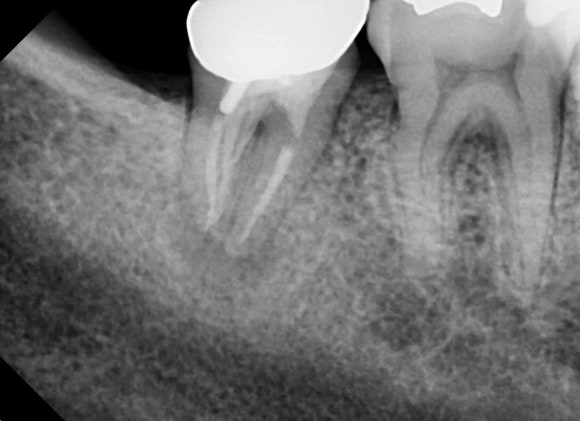

(좌)이전치료 (우)재신경치료 후

이전치료보다 더욱 꼼꼼하게 치료해야합니다.

많은 시간이 걸리고

여러번 오셔야 합니다.

환자분의 협조가 적극적으로 요청되는 치료입니다.

길고 지루하지만

자연치를 지켜낸다는 소중한 열매를 맺기 위해서

서로가 노력해야 합니다.